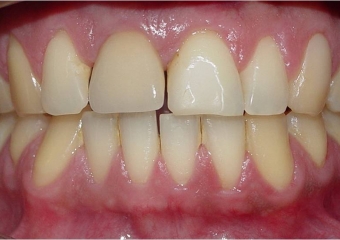

Imagens de 05 anos de controle, realizadas dia 01/04/2013